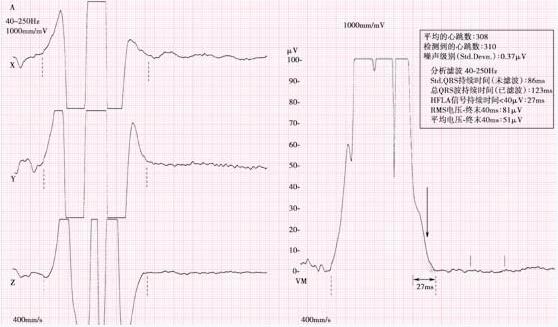

图8-2-3 心室晚电位图 心电图示QRS波主峰后可见高幅碎裂尖波,为右束支阻滞的右心室相对延迟除极波,并非真正心室晚电位信号(红箭头所示),从QRS波终末延伸到ST段内可见明显高频、低幅的多形尖波信号,才是真正的心室晚电位信号(黑箭头所示),25~250Hz滤波条件下,QRSD(滤波后QRS时限):225ms,HFLASD40(滤波后QRS波终末电压低于40μV高频低幅信号的持续时间):128ms,RMSV40(滤波后QRB终末40ms的平均根电压):4μV;40~250Hz滤波条件下,QRSD:220ms,HFLASD40:137ms,RMSV40:3μV。 诊断:心室晚电位阳性